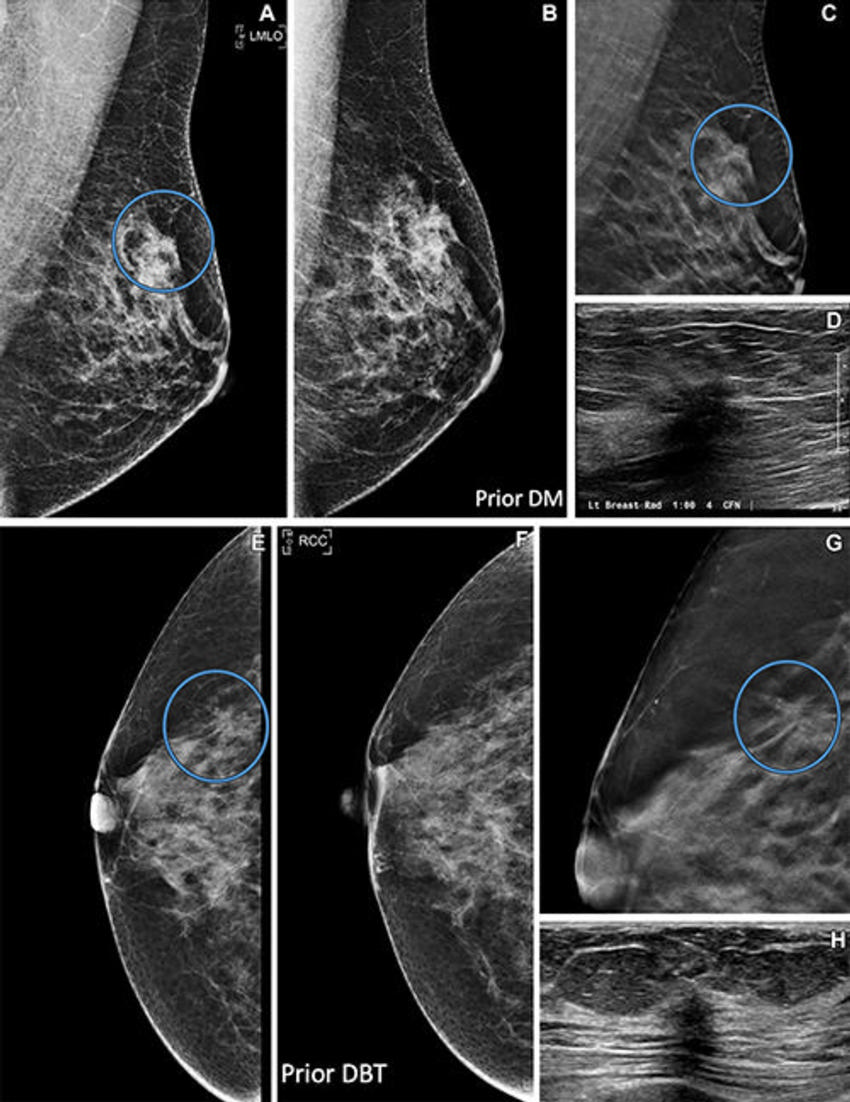

Figure 3. Images in (A–D) a 48-year-old female patient and (E–H) a 65-year-old female patient. (A) Left mediolateral oblique (LMLO) prevalent digital breast tomosynthesis (DBT) screening image shows an irregular mass (circle). (B) Prior screening digital mammogram (DM) suggests the mass may have been present but was not depicted. (C) DBT section image shows spiculated margins (circle). (D) US image shows a corresponding irregular hypoechoic mass. A 2.4-cm estrogen receptor– and progesterone receptor–positive, human epidermal growth factor receptor–negative invasive ductal carcinoma was found at pathologic evaluation. (E) Incident DBT screening image shows a new mass in the right breast (circle). (F) Previous DBT scan shows no finding. (G) DBT section image shows spiculated margins (circle). (H) US image shows a small irregular hypoechoic mass. A 0.6-cm estrogen receptor– and progesterone receptor–positive, human epidermal growth factor receptor–negative invasive ductal carcinoma was found at pathologic evaluation. RCC = right craniocaudal.